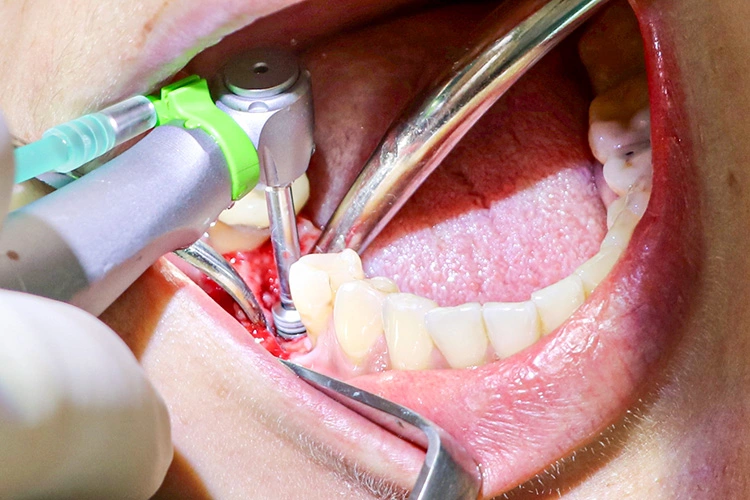

Im nächsten Schritt erfolgte die vollständig navigierte Implantation des Microcone-Implantates (Ø 5,0 mm, 9 mm Länge) in der Region 46 (Abb. 8-14) nach dem vom Hersteller empfohlenen Bohrprotokoll, das sich nach Knochenqualität und Implantatdurchmesser richtet. Die Chirurgie-Kassette (Abb. 6) ist übersichtlich aufgebaut und intuitiv zu bedienen. Zur schonenden Präparation des knöchernen Implantatbetts stehen je nach Implantatdurchmesser und Knochenqualität bis zu fünf verschiedene Bohrertypen mit Farbcodierung zur Verfügung. Das Implantat war für eine gedeckte Einheilung vorgesehen und der Kieferkamm wurde durch Nahtlegung speicheldicht verschlossen (Abb. 15).